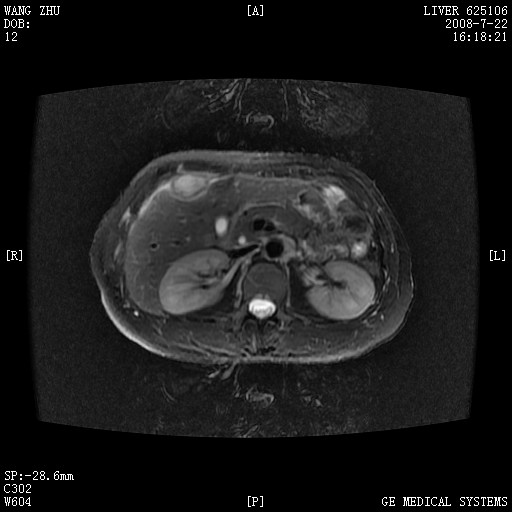

图像有点乱,病灶边缘清楚,可见纤维囊壁,灶旁可见异常灌注,增强显著增强,病灶有早期完全充填,无快退征像,考虑炎性病灶,肝结核可能性大,不知有何病史

肝前外缘见一类圆形囊性病灶,边缘强化,灶周肝为炎性渗出改变,其肝周可见少量腹水,符合炎性病变,病史较长---考虑腹膜结核。肝为外压性改变,脾为动脉期改变。